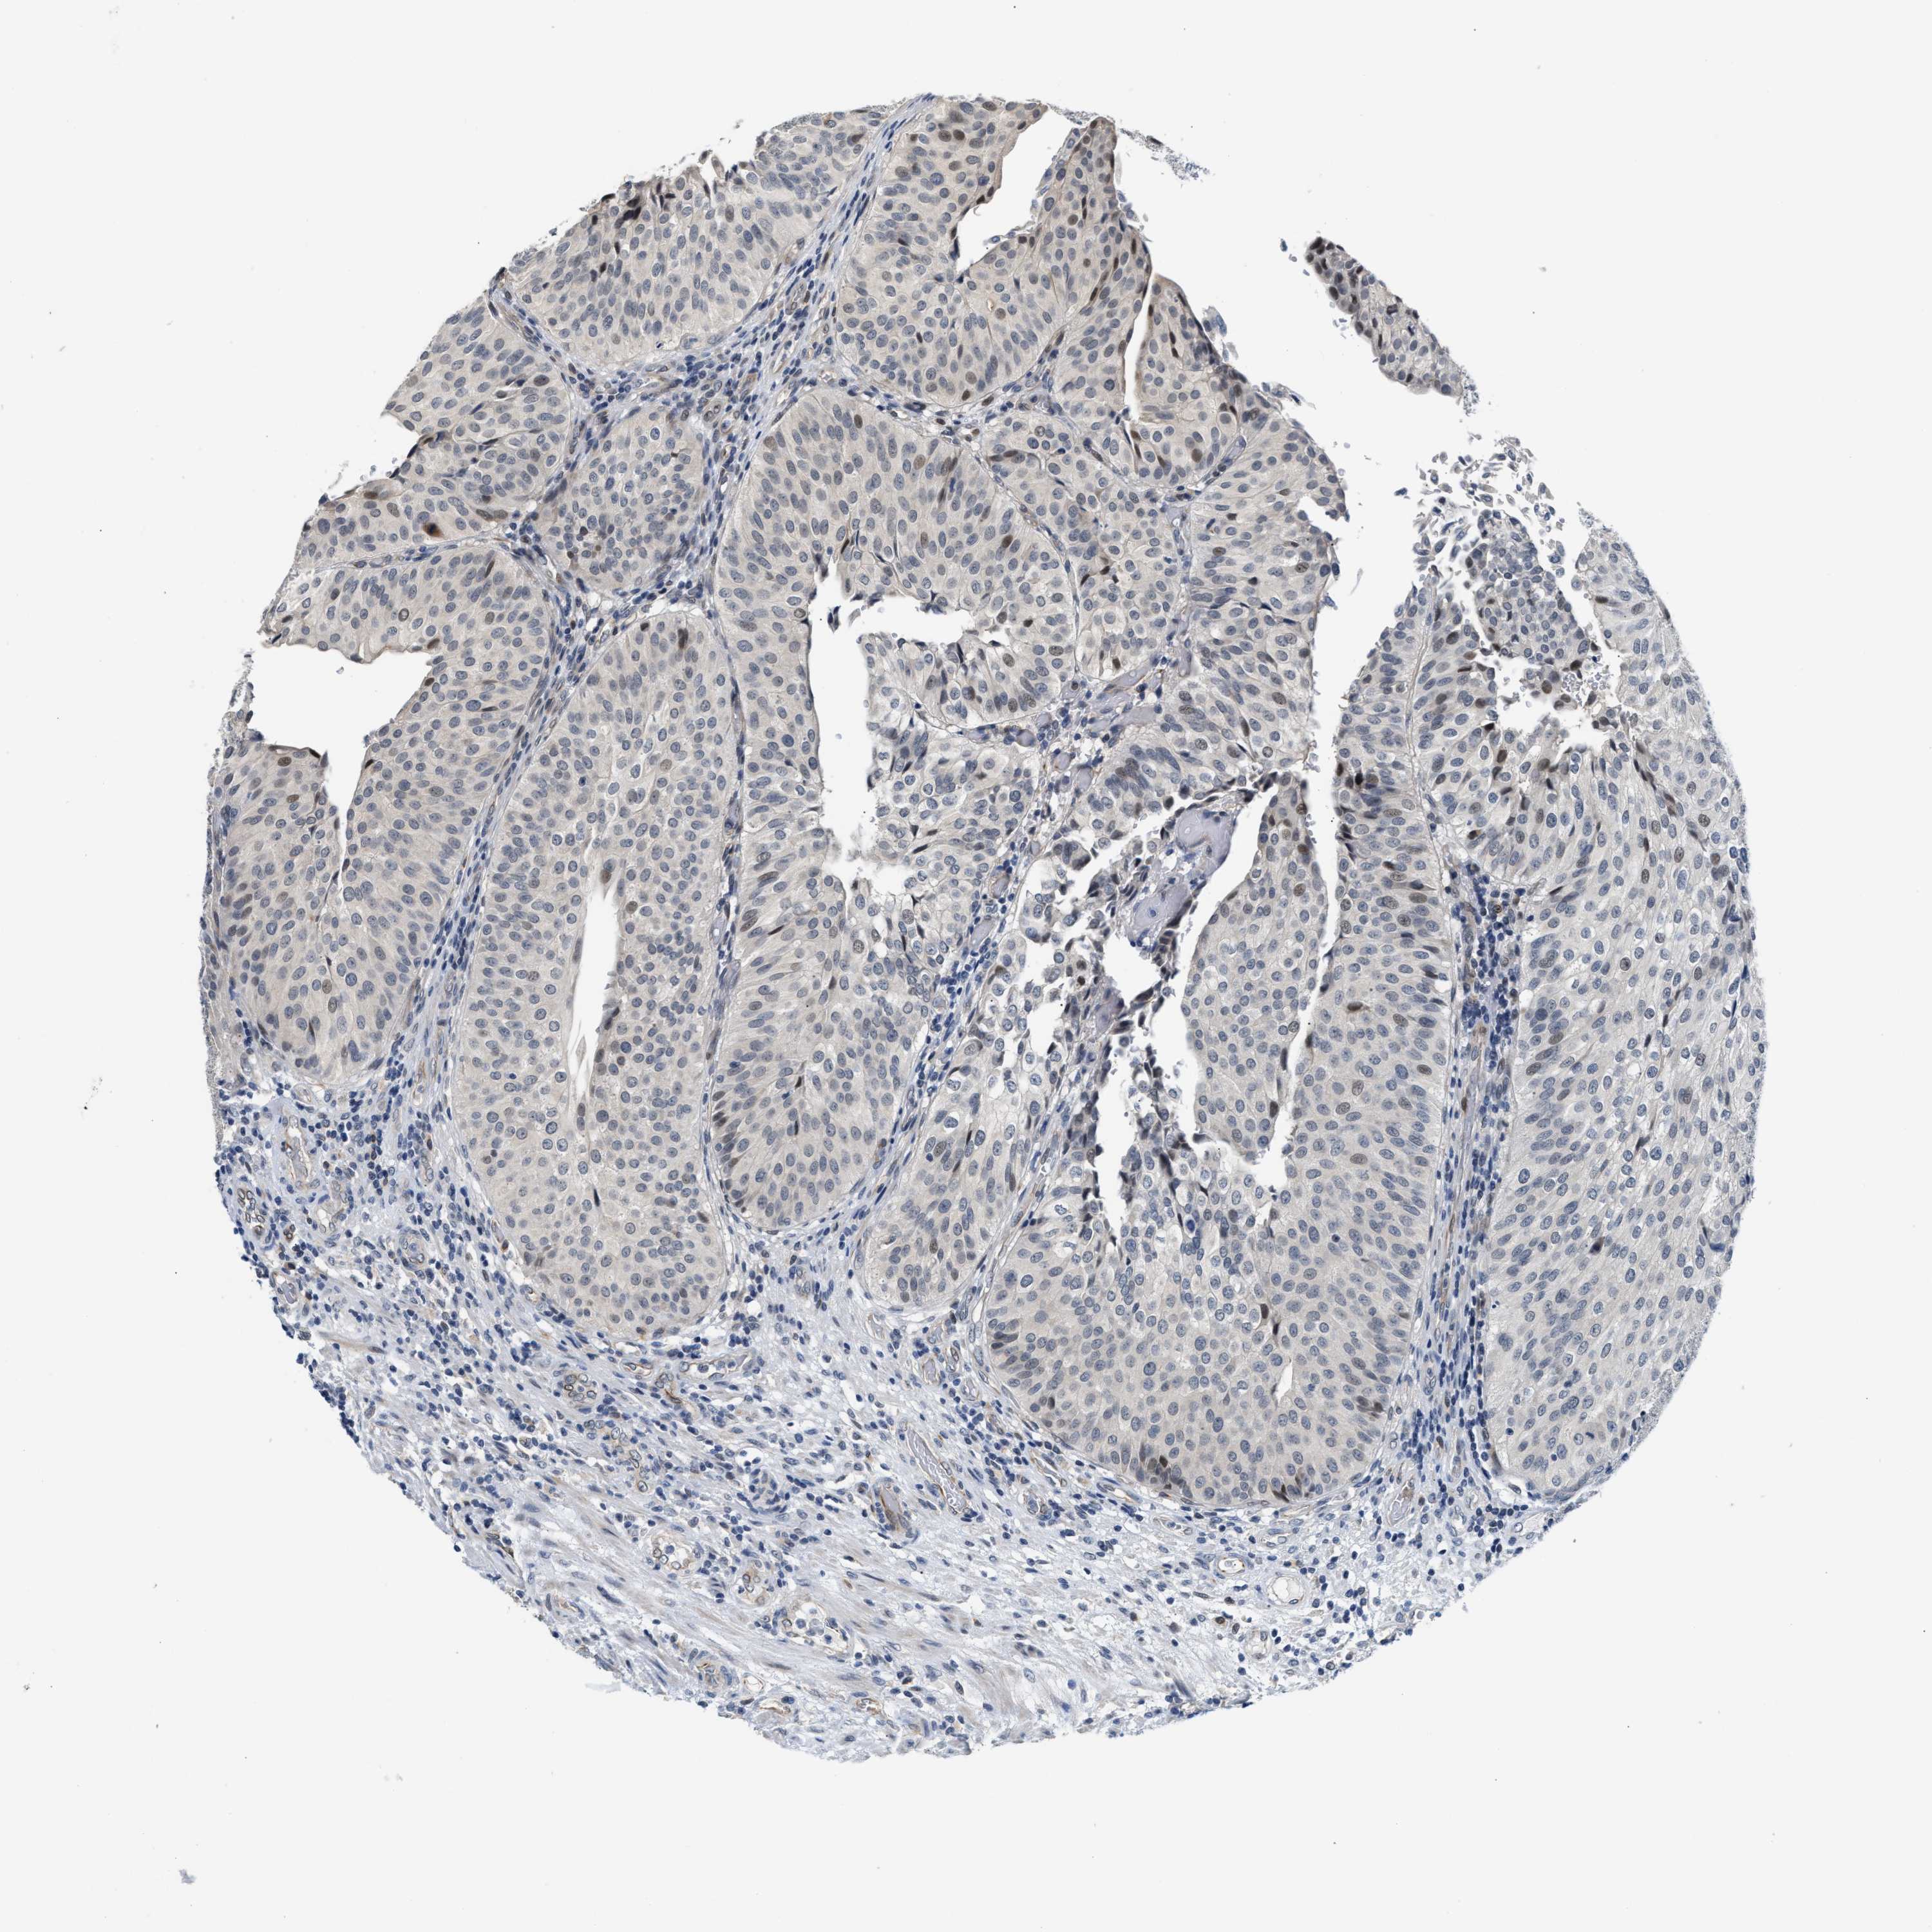

UROTHELIAL CANCER - Protein expressioni

A mouse-over function shows sample information and annotation data. Click on an image to view it in a full screen mode. Samples can be filtered based on level of antibody staining by selecting one or several of the following categories: high, medium, low and not detected. The assay and annotation is described here.

Note that samples used for immunohistochemistry by the Human Protein Atlas do not correspond to samples in the TCGA dataset.

Antibody stainingi

Antibody staining in the annotated cell types in the current human tissue is reported as not detected, low, medium, or high, based on conventional immunohistochemistry profiling in selected tissues. This score is based on the combination of the staining intensity and fraction of stained cells.

Each image is clickable and will lead to virtual microscopy that enables deeper exploration of all samples and also displays staining intensity scores, fraction scores and subcellular localization as well as patient and tissue information for each sample.

Antibody HPA044244

Antibody HPA058777

Antibody CAB020694

Staining

High

Medium

Low

Not detected

Intensity

Strong

Moderate

Weak

Negative

Quantity

>75%

75%-25%

<25%

None

Location

Nuclear

Cytoplasmic/membranous

Cytoplasmic/membranous,nuclear

Urothelial carcinoma, High grade

Urothelial carcinoma, Low grade

Urothelial carcinoma, NOS